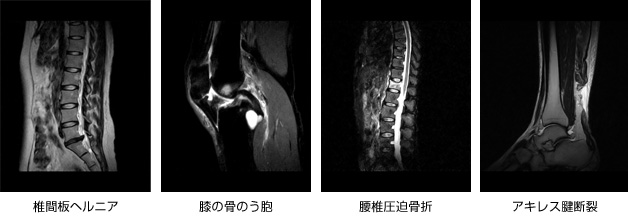

関節唇および肩甲上腕靱帯の正常変異とMRI画像所見のポイント。医療機関の方へ|御池クリニック。SLAP損傷 | ラドライフ。「関節のMRI」上谷 雅孝 / 青木 隆敏 / 神島 保定価: ¥ 13000#上谷雅孝 #上谷_雅孝 #青木隆敏 #青木_隆敏 #神島保 #神島_保 #本 #自然/医療・薬学・健康裁断済みのため全体的に状態が悪いとしております。口腔外科学 第4版 医歯薬出版 裁断済み。。医療機関の方へ|御池クリニック。素人裁断であることをご了承ください。また、本商品の他にも多数医学書を出品しておりますので、合わせてご検討ください。【koro】イラスト解剖学 改訂10版 最新版